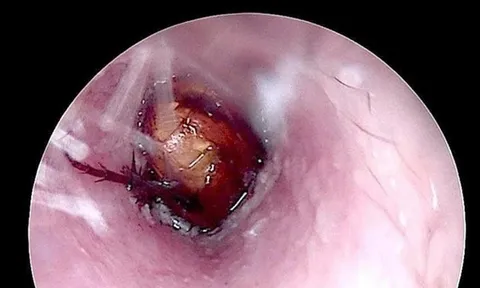

Ảnh minh họa

Cà chua là thực phẩm giàu dinh dưỡng và mang lại nhiều lợi ích cho sức khỏe. Ảnh minh họa.